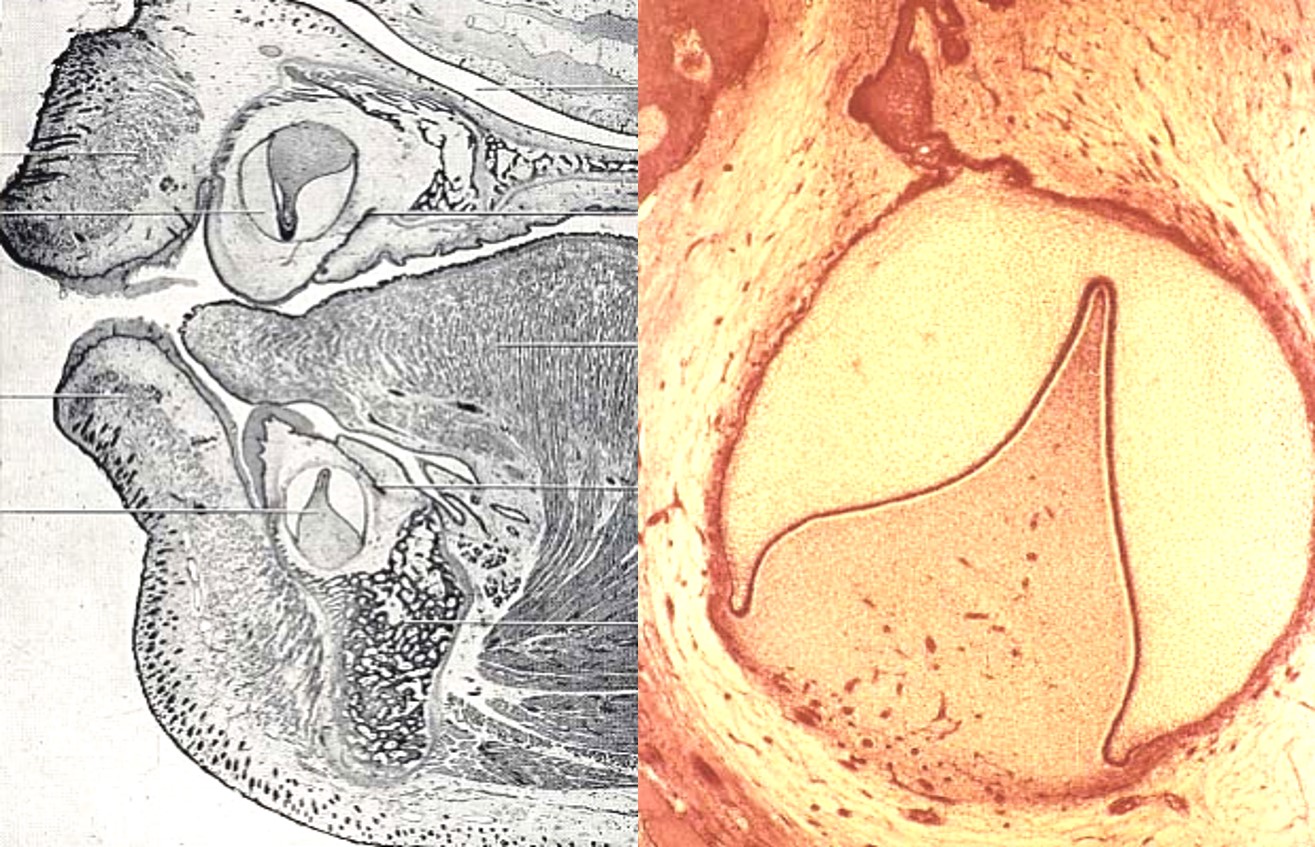

★2)帽状期(capstage)

胚胎第9~10周,上皮芽继续生长,体积增大,上皮周围的外胚间充质细胞增加,形成细胞凝聚区,随后上皮芽基底部向内凹陷,形状如帽子,覆盖在细胞凝聚区上。该期能区分牙的组成部分和支持组织。成釉器,牙乳头,牙囊,★形成牙胚的三个组成(图2.1-3)。

成釉器分化为三层细胞,外釉上皮层、内釉上皮层和星网状层。

在帽状期和钟状期牙胚中出现一些短暂的结构即釉结、釉索和釉龛。这些结构不是每个牙胚必须存在或同时出现的。牙板形成凹凸不平的薄层结构,结缔组织填充期间,称为釉龛(enamelniche)。在内釉上皮中央可见簇状未分化上皮细胞,称为釉结(enmelknot)(调控牙尖的形态发生)。釉结处有一条从内釉上皮延伸至外釉上皮的条索结构,称为釉索(enamelcord)。